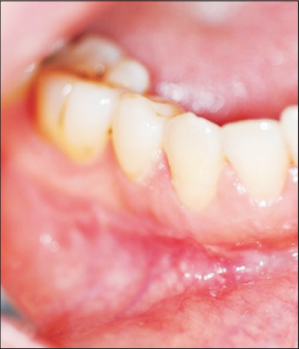

患者56岁,一月前发现牙龈肿痛,二周前进食时有不适感。患者有糖尿病。

口内检查发现患者右下颌前磨牙颊侧前庭处可见一肿胀,约2*1.5cm大小,质韧,扪诊无疼痛。颈部及颌下淋巴结未见肿大。 全景片未见明显异常。 CT显示右下颌第一前磨牙处有一约2cm大小低密度肿块